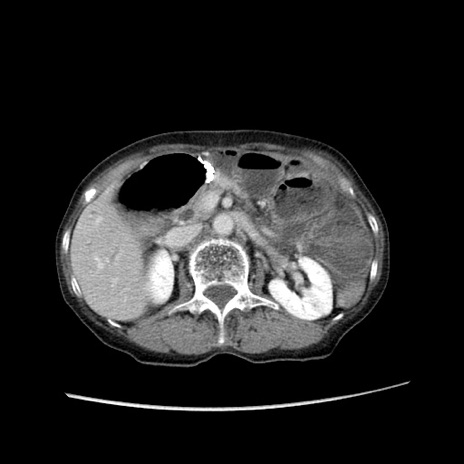

症例25(横断像)

【症例】80歳代女性

【主訴】胸のつかえ感

【現病歴】約9時間前に食後から胸のつかえた感じあり、嘔吐あり、来院。

【既往歴】胃癌(全摘)、胆摘、虫垂炎

【身体所見】心窩部に圧痛あり、反跳痛なし。

【データ】WBC 5700、CRP 0.05